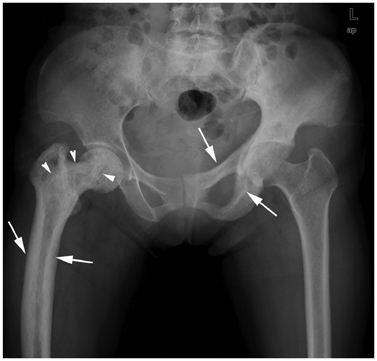

Systematic Approach of Sclerotic Bone Lesions Basis on Imaging Findings

- Sclerotic bone lesions are common, but there are diverse groups of tumors and non-tumorous lesions. Although plain radiograph and computed tomography can reveal important characteristics of these lesions, diagnosis is often challenging for radiologists. A systematic approach and familiarity with the imaging features of various sclerotic bone lesions may be greatly helpful for eliminating in the differential diagnosis. This review describes the systematic approach to diagnosing sclerotic bone lesions based on imaging findings.